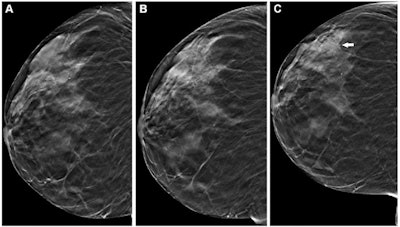

A retrospective analysis of over one million mammograms and over 500,000 digital breast tomosynthesis (DBT) exams published May 30 in Radiology found that DBT yielded more success than digital mammography across multiple screening rounds.

A team led by Brian Sprague, PhD, from the University of Vermont in Burlington found that DBT leads to lower recall rates and could help detect more cancers than mammography across three screening rounds. However, the two modalities did not have any significant differences in interval or advanced cancer detection rates.

DBT has been commercially available in the U.S. for more than a decade. An October report found that nearly half of mammography facilities accredited by the U.S. Food and Drug Administration (FDA) use the technology. Previous research suggests that DBT leads to higher cancer detection rates and lower recall rates compared with conventional mammography.